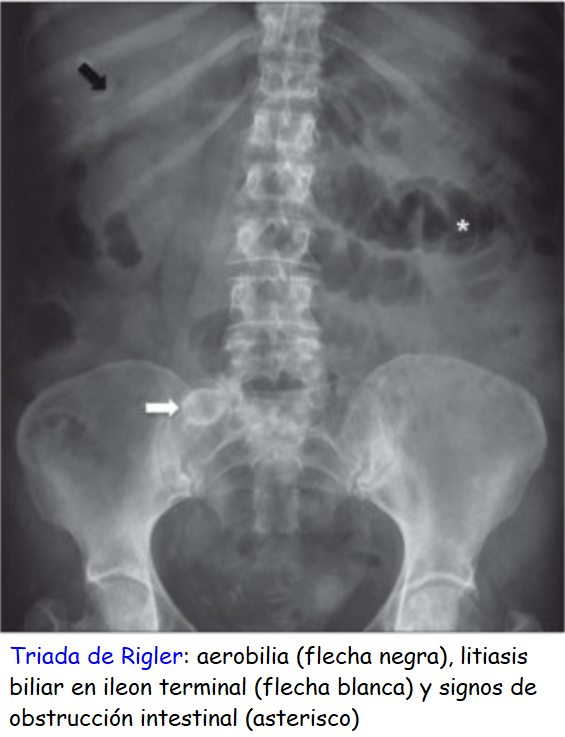

• La placa simple de abdomen de pie; en el caso de íleo biliar, en el cual el lito que pasó al duodeno a través de una fístula bilioentérica se “atora” en la válvula ileocecal. Cuando la obstrucción se encuentra en el intestino delgado no se observa aire en el colon en ninguna de las placas tomadas.

• Signo del grano de café: Cuando la causa es un vólvulo del sigmoides

• Signos de complicación: Pneumatosis intestinal (signo de Leo Rigler), ­

• Neumoperitoneo (aire debajo del diafragma, generalmente sobre el hígado).